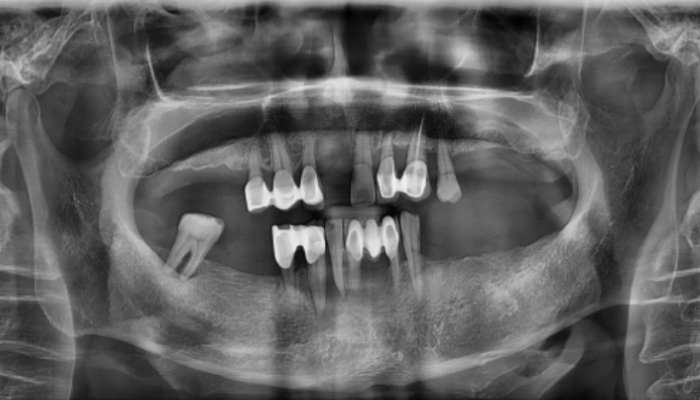

뼈이식 임플란트 전후 사례

• 식립전

식립후